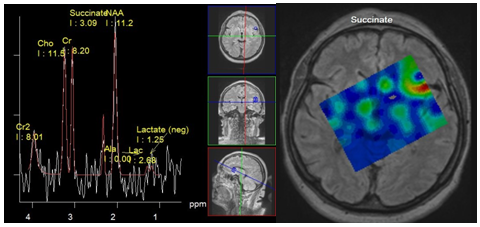

Neuroinfection: abscess, empyema: Brain abscesses are focal accumulations of pus surrounded by a capsule, developed from localized infection in the brain parenchyma (cerebritis). Subdural empyemas are accumulations of pus in the subdural space, which sometimes occur as complication of inflammation of the meninges (meningitis). Microorganisms that lead to the formation of abscesses are diverse and often include mixed culture: aerobic, anaerobic, facultative aerobic and facultative anaerobic bacteria.

Spectroscopy of pyogenic brain abscess and empyema demonstrate presence of specific metabolites such as succinate, acetate, alanine, valine, leucine, isoleucine, lactate and lipids, which makes it possible to differentiate them from other brain cystic lesions (Figure 5 & 6) High levels of lactate, acetate and succinate can be explained by increased glycolysis and fermentation of microorganisms. Such amino acids, as valine and leucine are the final product of proteolysis by enzymes released by neutrophils in pus.14 Neurons in abscesses are absent, so peaks of NAA and Cr should not be detected. The presence of these peaks can be explained only by misplaced voxels, or its contamination from adjacent parenchyma. Also, an acetate peak, which is close to NAA resonance frequency (Ac - 1.95 ppm, NAA - 2.01 ppm), can be erroneously attributed to the latter. Cho is also absent in the abscess cavity, since the necrotic core lacks membranes.

Figure 6 Meningitis. Spectra obtained from Lateral sulcus area near the small subdural empyema, PRESS, TE 135 ms (a) Map of succinate concentration. The peak of succinate 2.4 ppm can be seen (a), and its maximum concentration is localized in the sulcus (b).

Succinate (Suc): 2.43 ppm (singlet) product of the biochemical cycle of anaerobic microorganisms. Observed in pyogenic abscesses, empyema.